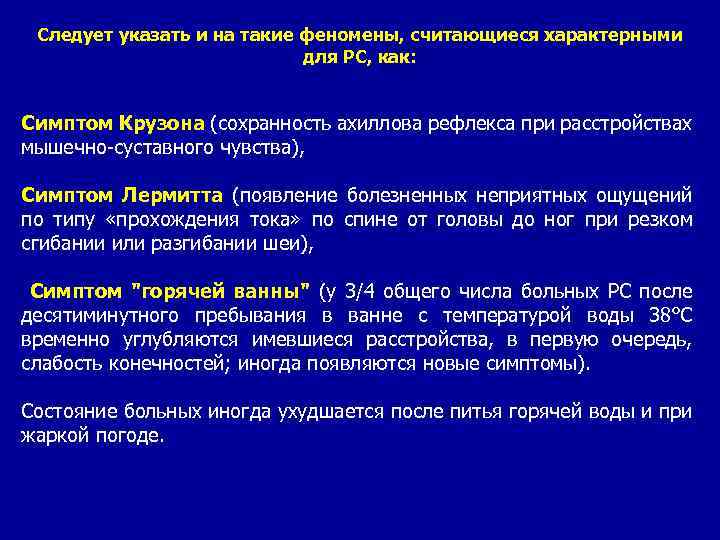

Следует указать и на такие феномены, считающиеся характерными для РС, как: Симптом Крузона (сохранность ахиллова рефлекса при расстройствах мышечно-суставного чувства), Симптом Лермитта (появление болезненных неприятных ощущений по типу «прохождения тока» по спине от головы до ног при резком сгибании или разгибании шеи), Симптом "горячей ванны" (у 3/4 общего числа больных РС после десятиминутного пребывания в ванне с температурой воды 38°С временно углубляются имевшиеся расстройства, в первую очередь, слабость конечностей; иногда появляются новые симптомы). Состояние больных иногда ухудшается после питья горячей воды и при жаркой погоде.